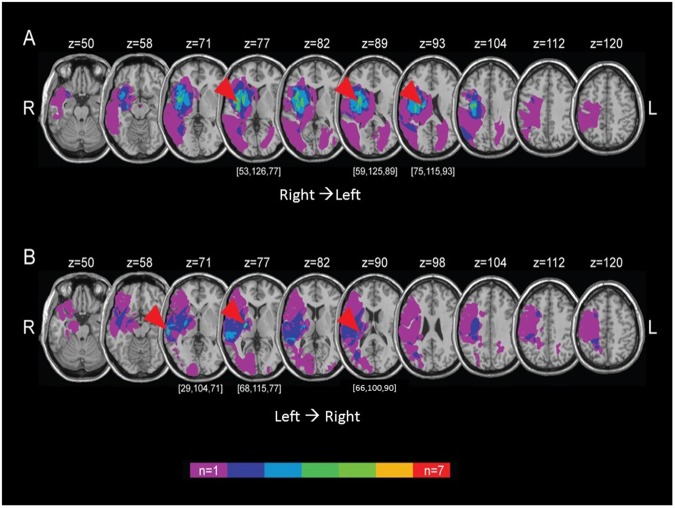

The lesion overlay of R → L patients revealed three primary regions of overlap: in the right putamen and claustrum (x = 53, y = 126, z = 77) appearing in four out of the seven patients, at the right insula (x = 59, y = 125, z = 89) appearing in five patients, and in the right caudate (x = 75, y = 115, z = 93) appearing in four patients, such that every R → L patient exhibited a lesion in at least one of these three foci (Fig. 2A). The lesion overlay of the L → R patients revealed two primary foci of convergence: five out of the seven patients exhibited a lesion in the right posterior limb of the internal capsule (x = 68, y = 115, z = 77) and four patients exhibited a lesion in the right middle temporal gyrus (x = 29, y = 104, z = 71), such that every L → R patient exhibited a lesion in at least one of these two foci (Fig. 2B). Taken together, underlying lesions in most patients from both R → L and L → R cultures were located in the right basal ganglia, as well as the right temporal/insular cortex. The spatial distribution of lesions is within the normal range for neglect patients, since the most frequent sites of damage in the right hemisphere involve temporal cortex and subcortical nuclei, along with inferior parietal lobule and ventral frontal region43,44.

Figure 2.

Lesion analysis. The spatial distribution of ischemic lesions (transformed into standard MNI stereotaxic space) in all R → L (A) and L → R (B) patients is demonstrated by overlaying the lesion masks onto a T1-weighted atlas. Voxels are color-coded in accordance with the number of patients with a lesion affecting a specific voxel. Arrowheads are directed at foci of lesion map convergences (x, y, z coordinates denoted in brackets).